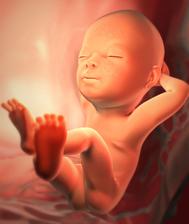

15.5. první KO u dr. potvrzeno těhotenství 6tt (gestační a žloutkový váček)

29.4. druhá KO u dr 7+3, 12,3mm a srdíčko bije